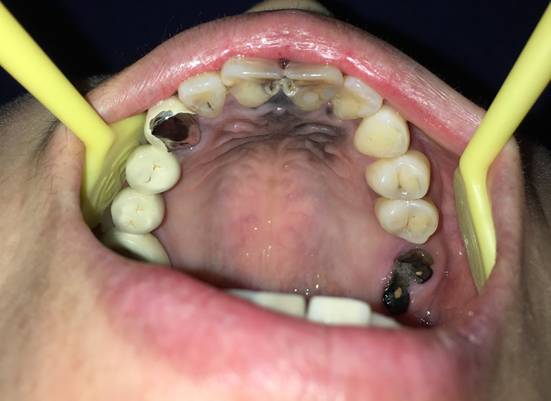

口腔治疗:口腔治疗包括补牙、装假牙等都会在口腔里放入一些材料,这些材料又会在口腔里存留很长时间,部分材料特别是镍铬合金,在口腔潮湿的环境里会被腐蚀,导致口腔黏膜发黑(图3)。

图3:口内装了多个镍铬合金的烤瓷牙,导致口腔天花板黏膜发黑。